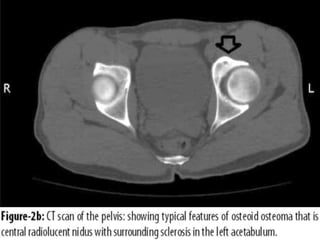

OSTEOID OSTEOMA

• Size: <2cm diameter

• Age: teens & twenties

• Site: appendicular skeleton

• Severely PAINFUL LESIONS, nocturnal,

dramatically relieved by aspirin (prostaglandin

E2 production by proliferating osteoblasts).

• Actual tumour called NIDUS.

• Surrounded by a broad zone of (sclerosis) reactive

bone formation on X-ray